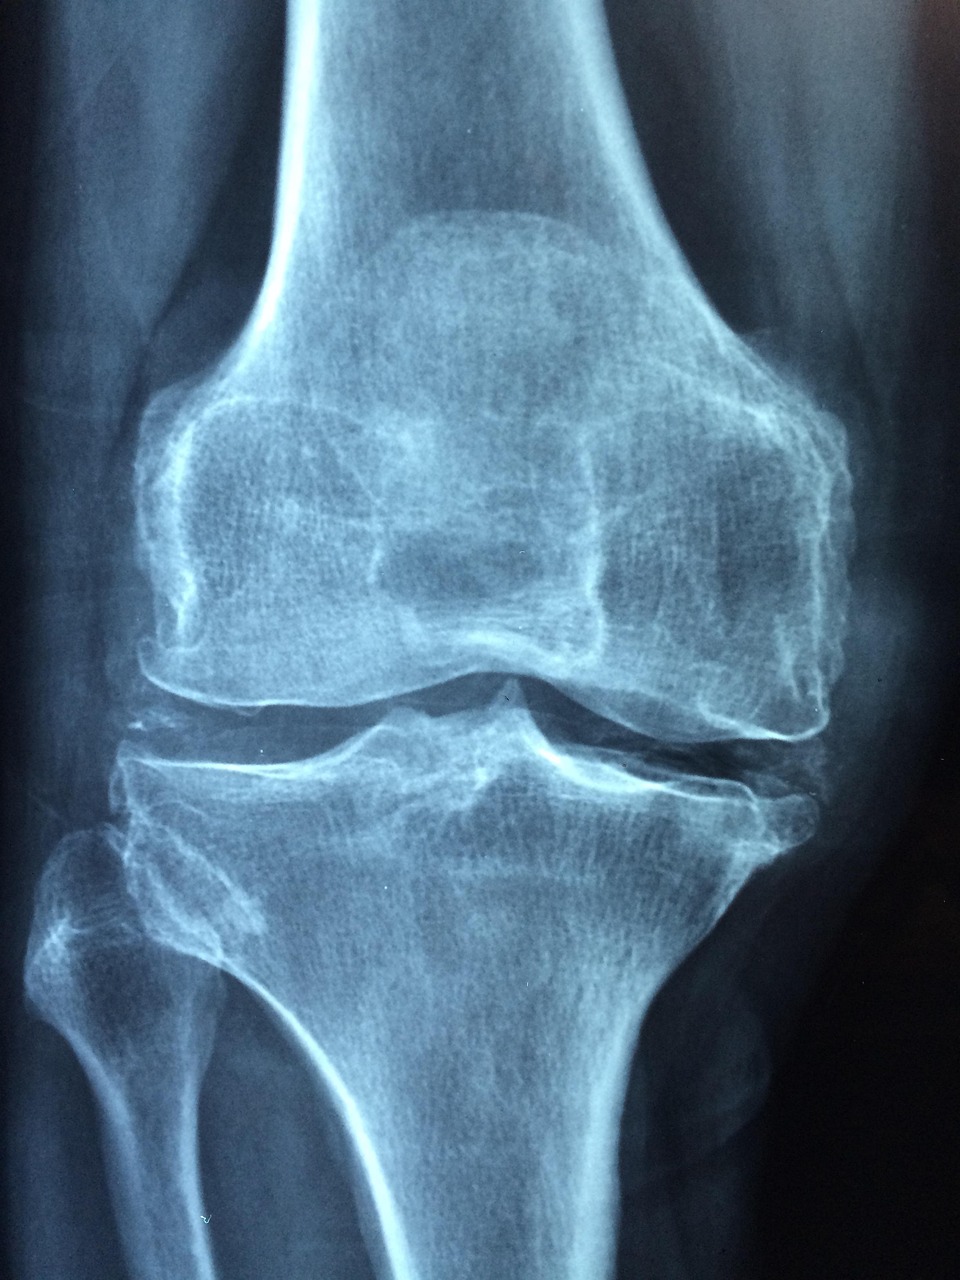

골다공증은 중년여성에게 매우 흔한 질환으로, 뼈의 밀도가 낮아지고 강도가 약해져 쉽게 골절이 발생하는 상태를 말합니다. 특히 폐경기를 겪는 여성은 에스트로겐 수치가 급격히 떨어지면서 뼈 손실이 가속화됩니다. 뼈는 신체의 기본 구조이자 생존에 필수적인 요소이므로, 한 번 약해지면 회복이 어렵고 회복 기간도 길어집니다. 따라서 조기에 예방법을 알고 실천하는 것이 건강한 노후를 위한 핵심입니다. 이 글에서는 중년여성들이 꼭 알아야 할 골다공증 예방을 위한 칼슘 섭취, 걷기운동, 그리고 일상 속 생활습관 개선에 대해 체계적으로 알아보겠습니다.

정기적인 건강검진과 골밀도 검사도 예방의 중요한 요소입니다. 골다공증은 자각증상이 거의 없어, 진단 전까지는 뼈 상태를 파악하기 어렵기 때문입니다. 50대 이후 여성이라면 최소 2년에 한 번은 골밀도 검사를 받고, 필요시 전문의 상담을 통해 조기에 치료를 시작하는 것이 좋습니다.